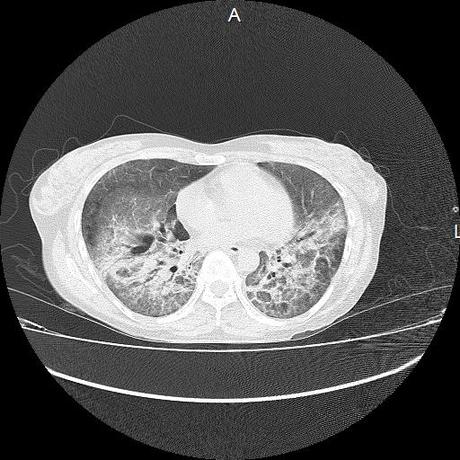

El parénquima pulmonar con areas parcheadas difusas en vidrio despulido combinadas con otras areas hipodensas de baja atenuación debidas a atrapamiento aéreo y engrosamiento intersticial y zonas de fibrosis de predominio en lóbulos medios e inferiores de ambos pulmones.

- LOS HALLAZGOS PUEDEN ESTAR EN RELACIÓN A NEUMOPATIA INTERSTICIAL PROBABLE ETIOLOGIA HIPERSENSITIVA VS AUTOINMUNE/BACTERIANA/FUNGICA.